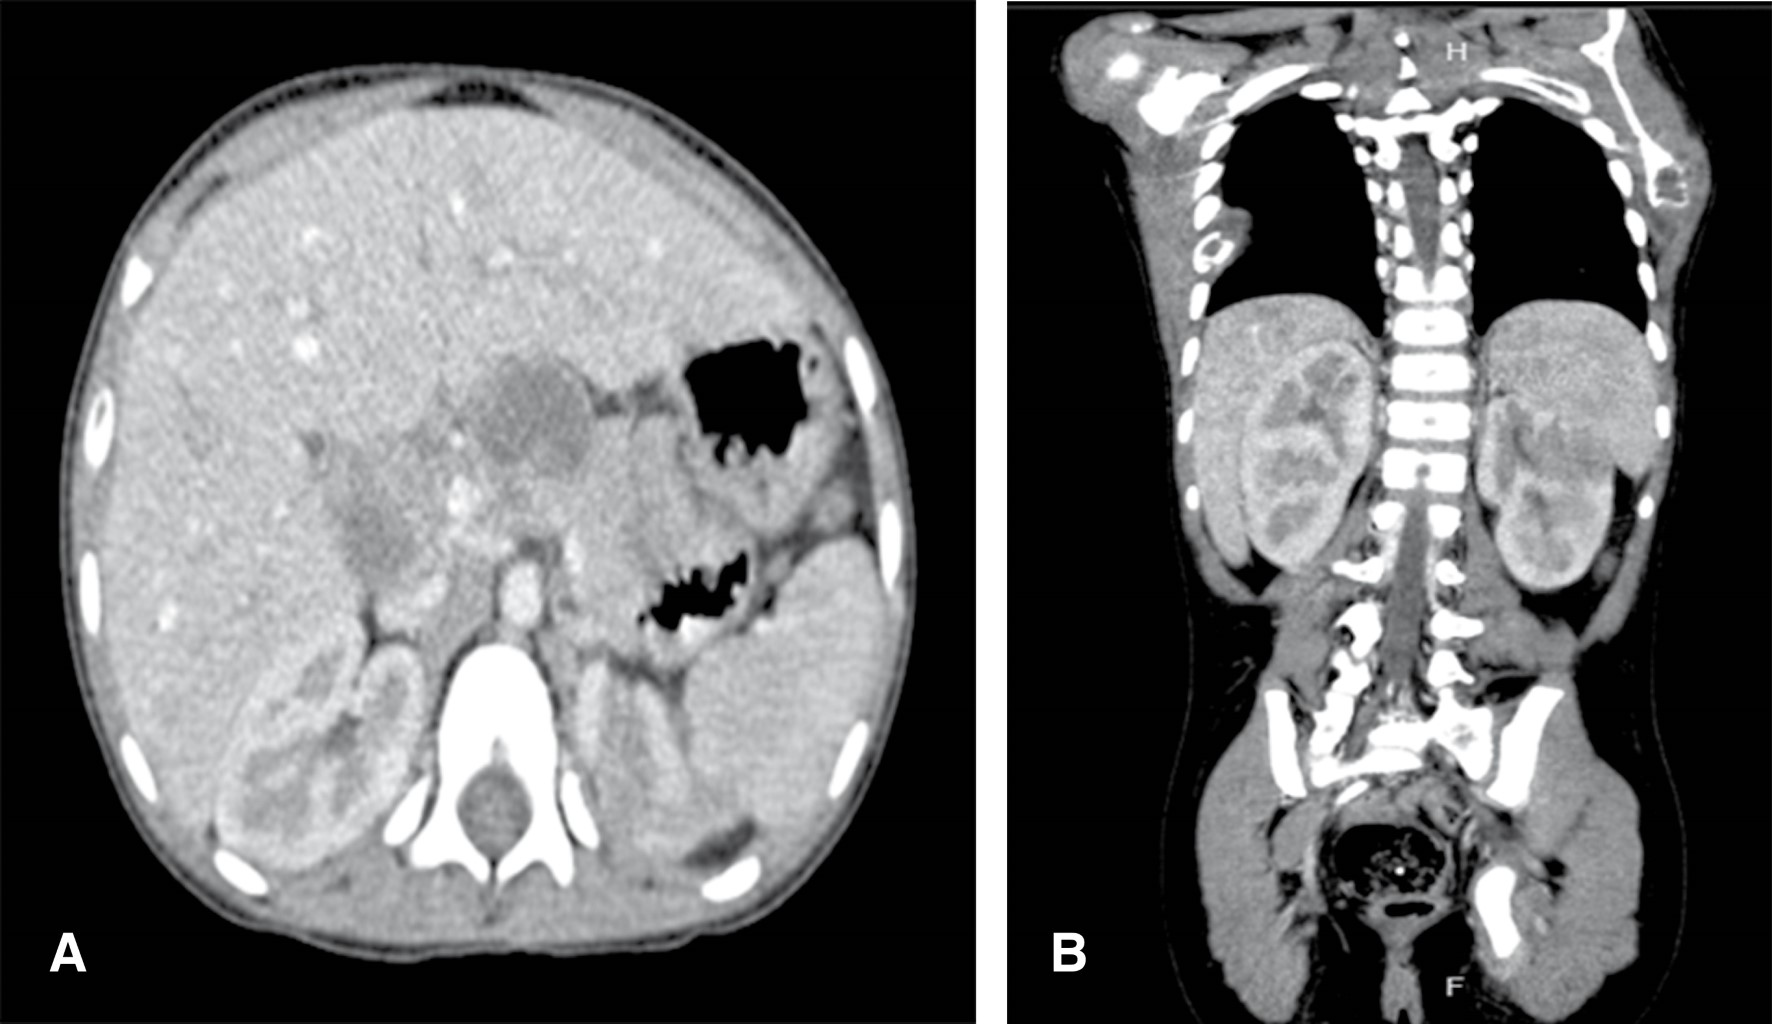

Paracoccidioidomycosis is a disease that generally occurs in adult men whose labor is associated with agricultural activities in Latin America. In this population the mycosis manifests in a chronic form. On the other hand, in the pediatric population its prevalence is lower, lung involvement is not common and it is expressed in an acute/subacute form. Next, we present the case of a 7-year-old female patient who was diagnosed with this mycosis by liver biopsy. The clinical and paraclinical findings and a literature review are described.

Figure 1

Figure 2